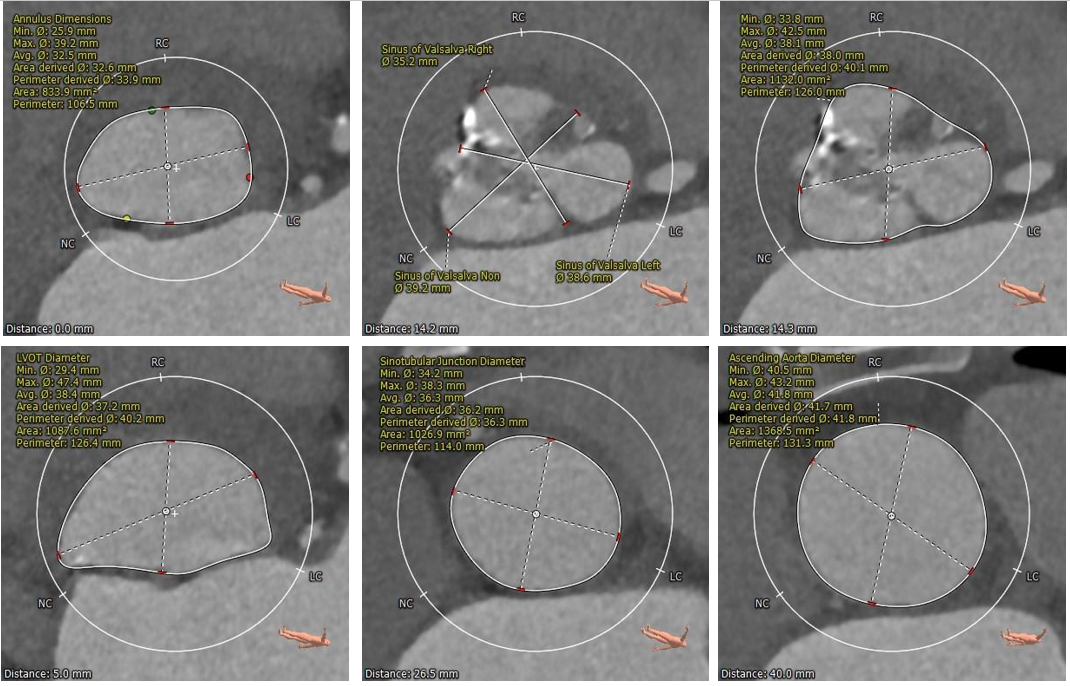

术前CT评估

•三叶式主动脉瓣,瓣环径为33.9mm,瓣环明显增大,瓣叶增厚伴重度钙化,钙化主要分布于瓣叶边缘,以右冠瓣为著;

•冠脉开口高度可,切线角度测量未见冗长瓣叶;

•瓦氏窦、窦管交界内径尚可,升主动脉扩张;

•左室腔内径明显增大,心室壁厚度尚可;

•瓣环水平夹角为62°,主动脉弓宽度、角度尚可;升主动脉轻度扭曲;

主动脉根部测量

瓣上结构测量